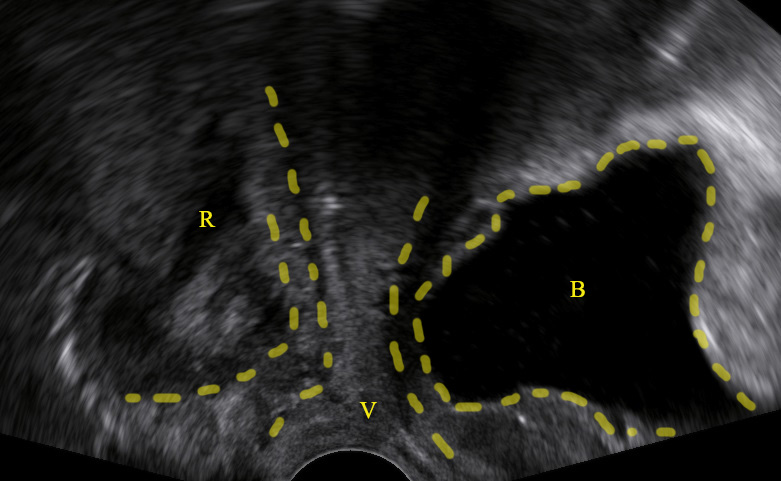

Types of cystocele:

Symptoms of anterior vaginal wall prolapse like incomplete bladder emptying or feeling of vaginal bulge are frequent when:

- The bladder descends at least 10mm below the symphysis pubis (pelvic floor sonography).